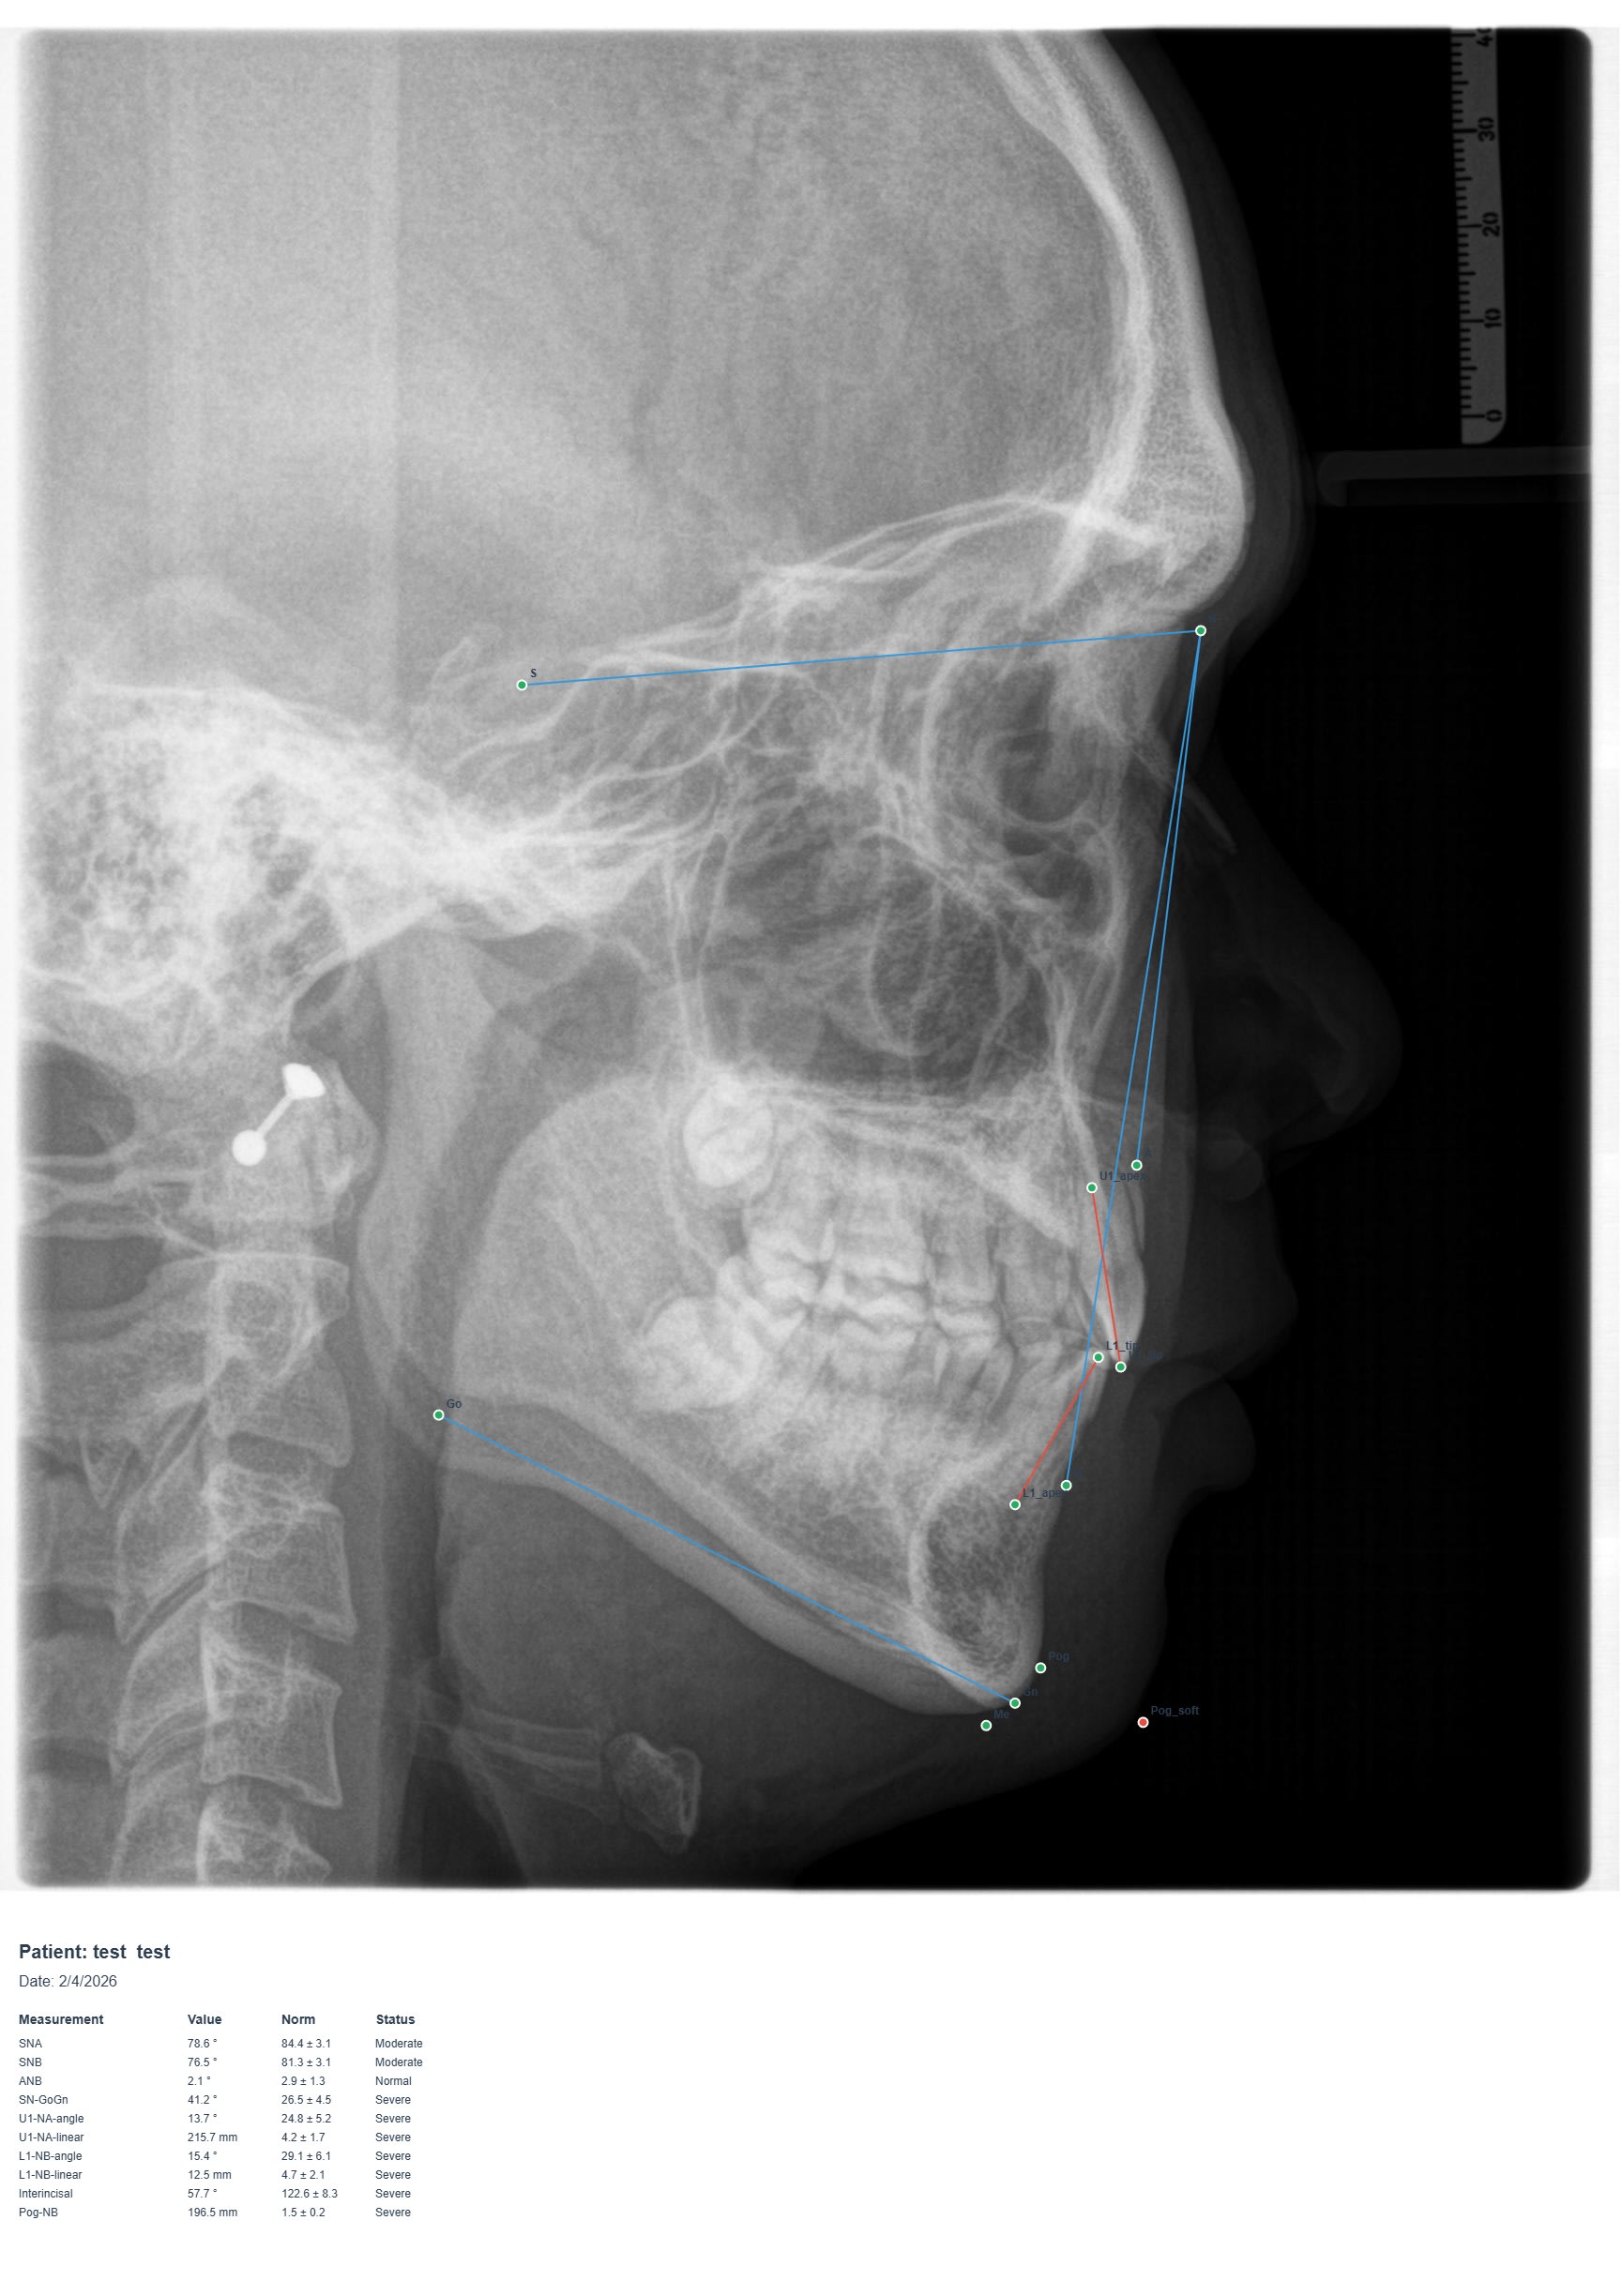

Et j'ai fait un petit logiciel de céphalometrie basic avec Claude.

Tu l'installe, tu crées un patient, importe la lateral ceph , positionne les points (tu peut les bouger après ou quand tu réouvre l'analyse ) , tu valide et ça te fait une jolie analyse avec traces et table de valeur plus indication si les valeur sont normal ou non.

Ok c'est basique mais c'est aussi littéralement le premier essais que j'ai fait. L'IA va être un gros bouleversement..

Les points que tu peux reprendre (éditer), j'avoue que c'est fort. En quoi tu l'as programmé? Quelle est l'analyse cephalo utilisée?

Quand tu dois reprendre un point, tu double cliques dessus? Tu peux mettre le source ici (tu modifies ton extension de fichier en .jpg, ca devrait passer!!!) ?

Aucune idée en quoi ça à était codé , j'ai décrit ce que je voulais à Claude + j'avais préparer de la doc sur l'analyse voulue et le valeur normal.

Oui tu peut déplacer les points à n'importe quel moment même avec une analyse déjà faite . Tu clique sur le point dans la liste et tu peut le bouger.